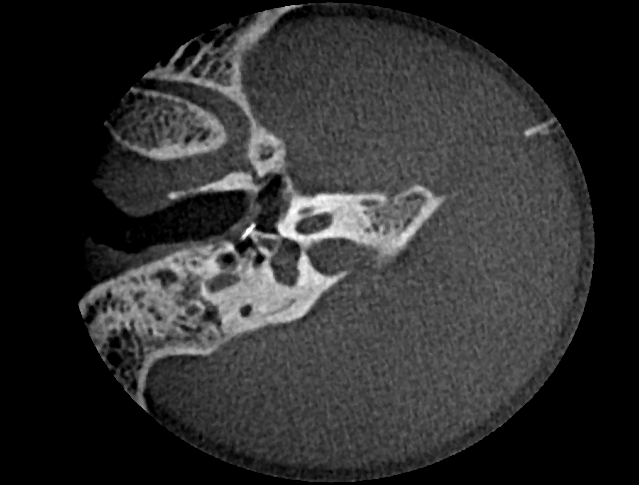

Ambossarrosion mit Stapesprothese Stapesprothese Teflon (Causse) PORP auf Stapes PORP Titan auf Stapes PORP PORP Titan disloziiert Otosklerose Otoskleroseherd TORP Pauke nicht belüftet TORP unter Knorpelinsel disl.